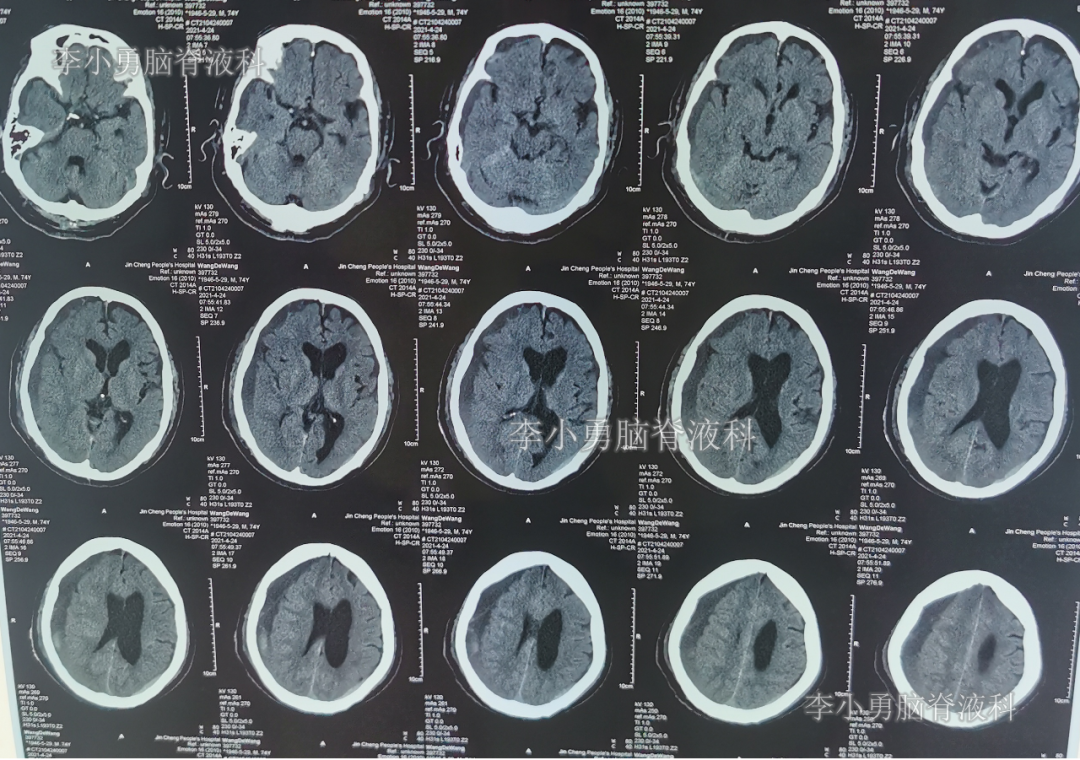

2021年4月17日(腰大池腹腔分流术后20天,硬膜下血肿引流术第1天),查头部CT示引流术后状态,仍有血肿(图-5)。

图-5:2021年4月17日头部CT

2021年4月19日(腰大池腹腔分流术后22天,硬膜下血肿引流术第3天),期间体位性头晕头痛、间断游走性腹痛也缓解,查头部CT示硬膜下血肿减少(图-6);给予拔除脑室外引流管。

图-6:2021年4月19日头部CT

拔除引流管后8天时间内,间断有右侧额颞部站立时疼痛,分别于2021年4月24日和2021年4月27日,查头部CT示硬膜下血肿增多(图-7、图-8),平卧位继续观察。

图-7:2021年4月24日头部CT

图-8:2021年4月27日头部CT